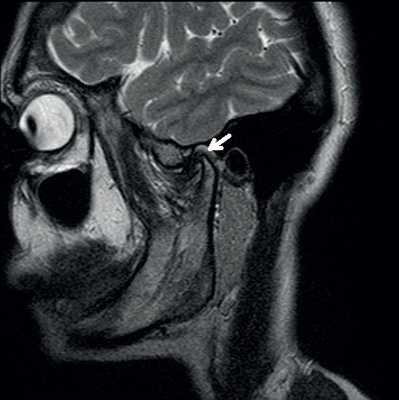

Злокачественная опухоль на МРТ

Злокачественные опухоли характеризуются инвазивностью, то есть врастанием в здоровые ткани, поэтому контуры таких образований нечеткие и неровные, а потому достоверно определять границы таких опухолей довольно сложно. Кроме того, структура злокачественной опухоли часто бывает неоднородна за счет распада (некроза), кровоизлияния и коллоидной дегенерации. Вокруг злокачественной опухоли, как правило, выявляется выраженный перифокальный отек, который может приводить к смещению срединных структур головного мозга и появлению аксиальной дислокации. Также могут быть выявлены признаки метастазирования.